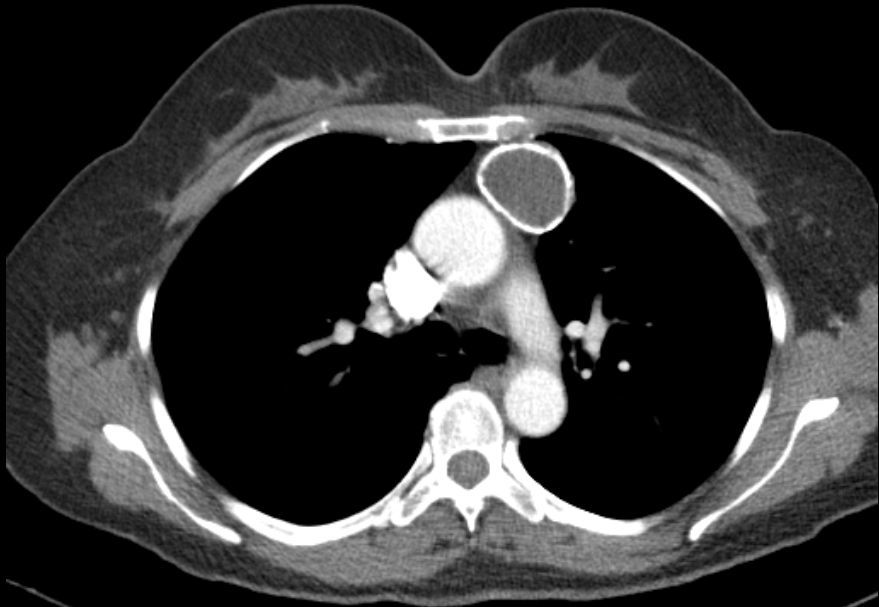

胸腺肿瘤的影像学评估及分期

图片尺寸1200x2576![【求助】前纵隔肿瘤 [病例帖]](https://i.ecywang.com/upload/1/img1.baidu.com/it/u=3916939084,2417362257&fm=253&fmt=auto&app=138&f=JPEG?w=388&h=500)